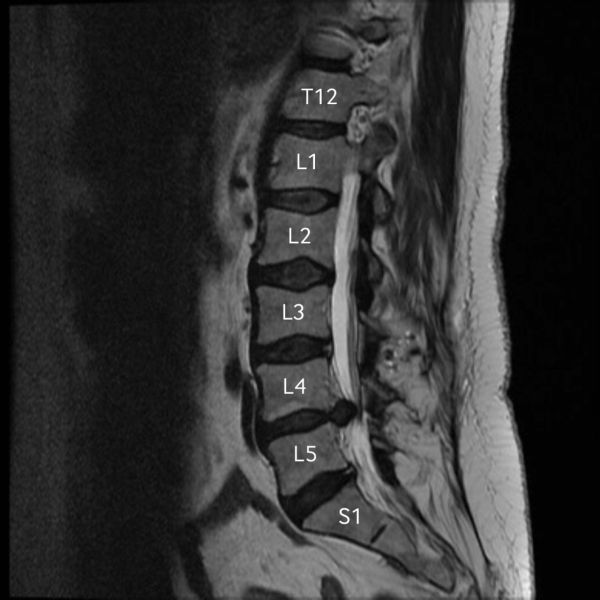

This was the beginning of what I recently found out would be a life-time struggle. Something I will have to "live with" for the remainder of my life. On that night in August of 2017, my life changed forever.

I live in chronic pain every single day of my life. I have upper and lower back pain, pelvic pain, knee, foot, elbow, wrist, and finger pain. I have pain when I stand up, lay down, walking, and sitting. I have chronic pain. It never lets up, and it never gives me a break.